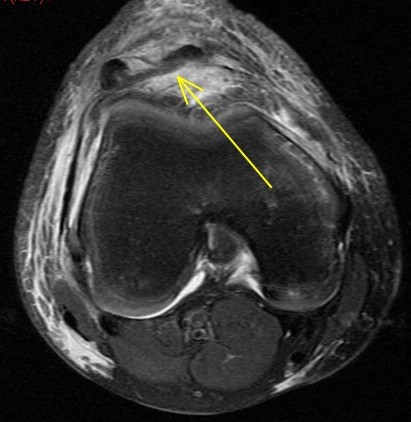

Trampoline injury, 10y/o

Wheeless: mechanism: eccentric contraction of the quadriceps on the flexed knee. occurs when the inferior pole of the patella of a child or adolescent is pulled off together with a large amount of articular cartilage and retinaculum. Superior patella pulled superiorly with chondral defect. Reference article.

Patellar sleeve avulsion